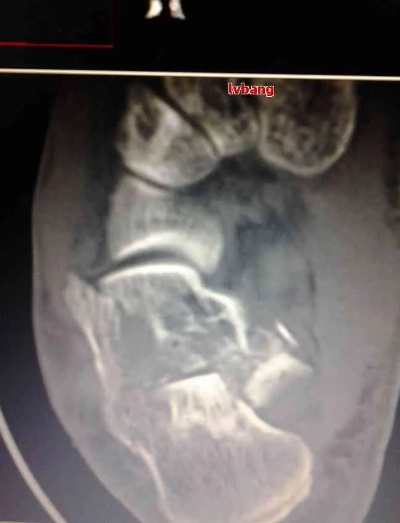

咱们先说说这个“距骨”,它在哪儿呢?就在咱们脚脖子(踝关节)那块儿,是个挺关键的骨头,承上启下,连接着小腿骨和脚上的其他骨头,咱们走路、跑步、蹦跳,它都得使劲,这地方一旦骨折了,那可不是小事儿,恢复起来也得格外小心。

老王是一家建筑公司的工人,在一次高空作业时不小心摔了下来,正好伤到了右脚脚踝,送到医院一检查,诊断为“右距骨粉碎性骨折”,医生说比较严重,得马上手术,打了钢板和钢钉固定。

鉴定专家仔细看了老王的病历、手术记录、复查的片子,又现场检查了他右脚的活动度、有没有压痛等情况,考虑到他是粉碎性骨折,做了内固定手术,虽然骨头长上了,但踝关节活动有一定受限,而且存在慢性疼痛,老王被鉴定为九级伤残。